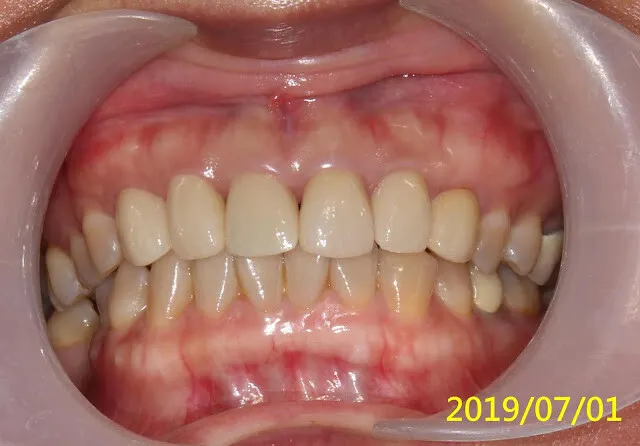

再經過一年,假牙看起來更自然了,當初剛裝假牙時的牙齦,病人自己說大概一個多月就自動長好恢復了

正中門牙的黑三角,無解,那是成人重做門牙或矯正常見的問題,因為已不像年輕人的牙齦那麼有再生活力與適應力,所以很多牙醫師都喜歡做連在一起的假牙,解決黑三角的問題(可參考她最上面的原始假牙),可這是對醫師方便、好,對病人的健康並不好。

我的預設值本來就是單顆獨立分開的假牙(只要條件允許)。